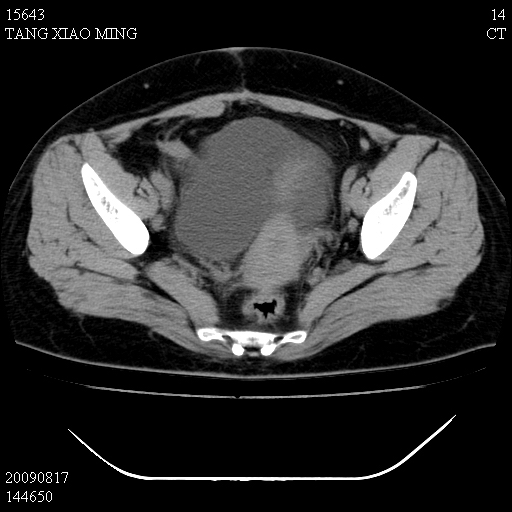

标题: CT21692:盆腔病变

女,33岁,右下腹痛2年余,既往宫外孕病史,如在我院手术,结果下周公布,

可能的诊断。1子宫内膜异位【子宫腺肌症并右卵巢巧克力囊肿】;2 右卵巢囊腺瘤。子宫肌瘤

1)考虑卵巢巧克力囊肿,不排除卵巢囊腺瘤。2)子宫肌瘤可能。

卵巢囊腺瘤,子宫肌瘤,直肠壁厚,不除外占位.